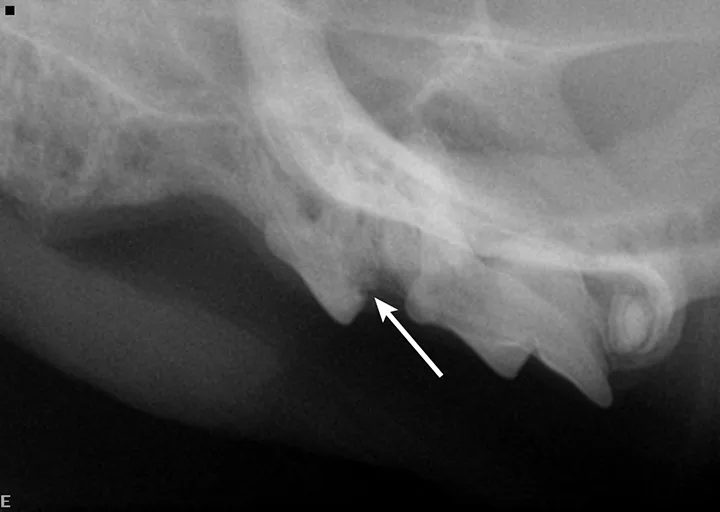

A complete oral examination and full-mouth dental radiographs were performed with the patient anesthetized. The detailed oral examination confirmed unhealed extraction sites with sharp crown fragments protruding from the alveoli into the oral cavity. In addition, an advanced TR lesion was noted affecting the left maxillary third premolar tooth (Figure 3). Dental radiographs confirmed advanced type 2 resorption affecting all involved teeth, as well as oral extension of the remaining tooth structure (Figure 4).

FIGURE 3

Intraoral radiograph of the left maxilla revealing type 2 tooth resorption on the third premolar (arrow). Extraction is indicated.

Dental radiographs are crucial in establishing proper diagnosis and treatment. Teeth with type 1 TR have normal root density in some areas, as well as a well-defined periodontal space. There is generally a clearly defined root canal in the intact part of the tooth. This type may involve significant resorption of the tooth and/or root(s) that is not replaced by bone. These teeth must be completely extracted.

Teeth with type 2 TR have undergone significant replacement resorption. In these cases, the lost root structure is replaced by bone. Therefore, teeth with type 2 TR have a different radiographic density as compared with normal teeth. Radiographic findings typically include areas with no discernible periodontal ligament space (ie, dentoalveolar ankylosis) or root canal. In advanced lesions, there is little to no discernible root structure (ie, ghost roots).